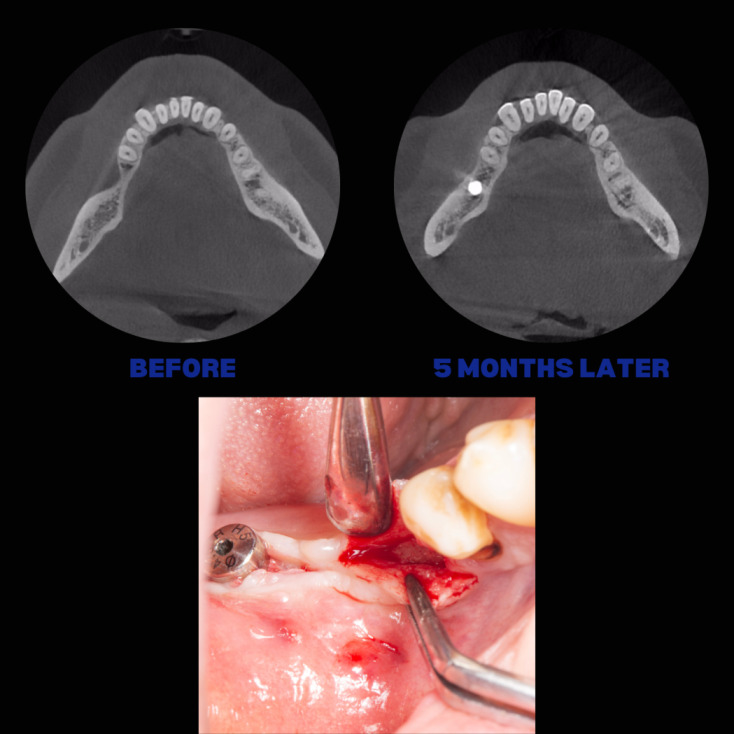

İmplant etrafındaki kemik açıklığını kemik grefti ile tedavi ettiğimiz vakamızdan biri